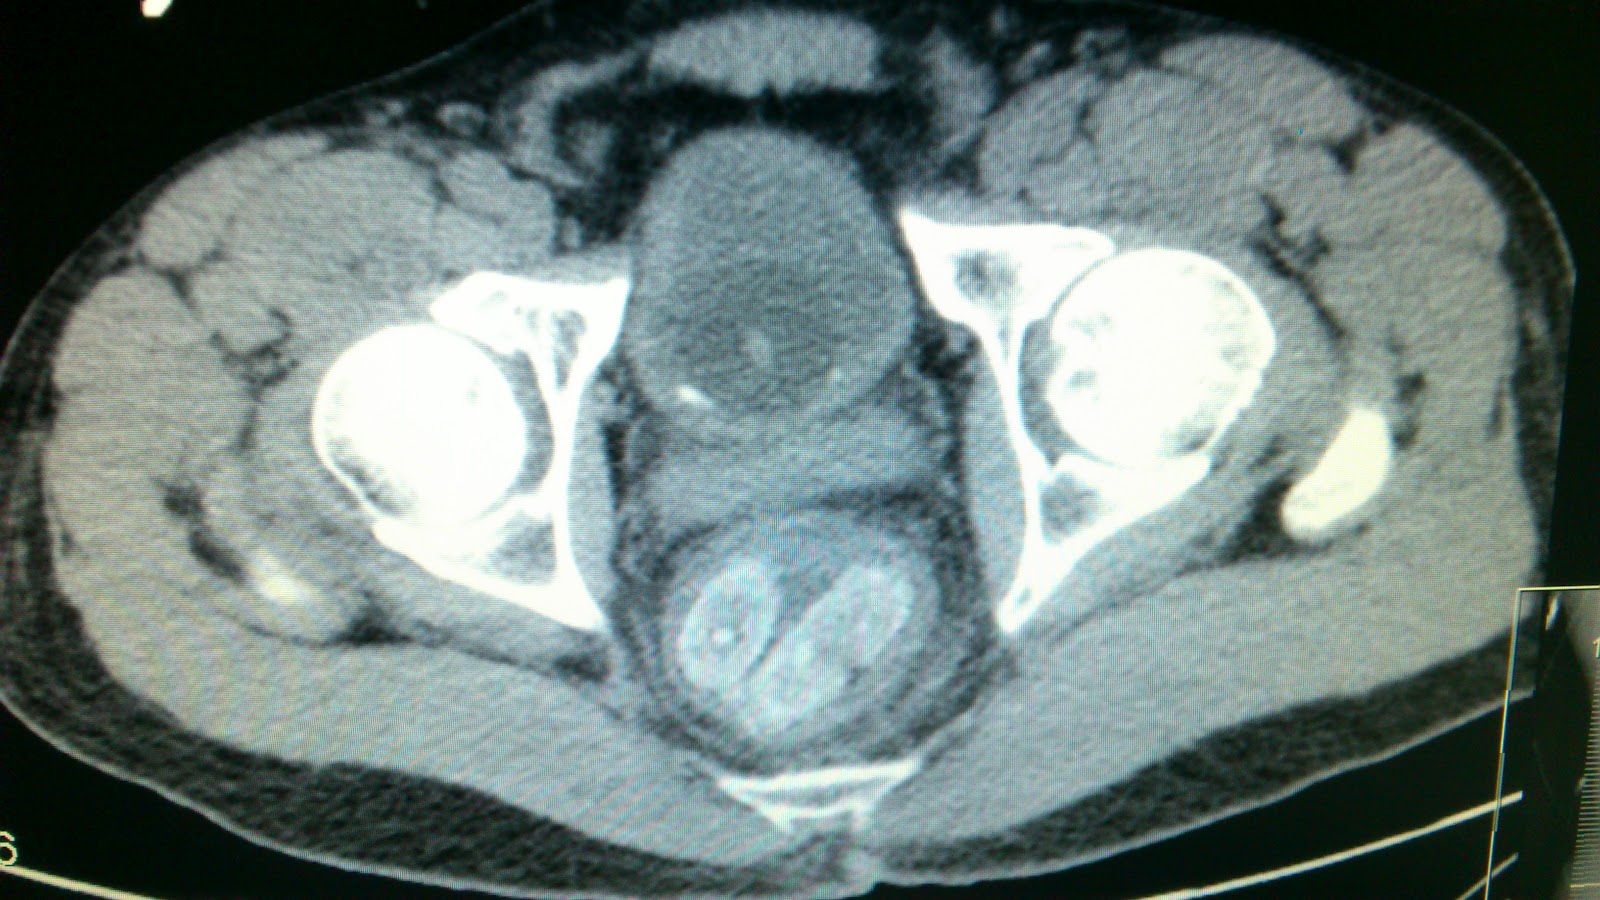

Resposta ao Caso de Urgência - Incidentaloma

A ureterocele is a congenital abnormality found in the urinary bladder. In this condition called ureteroceles, the distal ureter balloons at its opening into the bladder, forming a sac-like pouch. It is most often associated with a duplicated collection system, where two ureters drain their respective kidney instead of one. Simple ureteroceles, where the condition involves only a single ureter, represents only twenty percent of cases. Ureteroceles affects one in 4,000 individuals, at least four fifths of whom are female. Patients are frequently Caucasian.

Since the advent of the ultrasound, most ureteroceles are diagnosed prenatally. The pediatric and adult conditions are often found only through diagnostic imaging performed for reasons other than suspicious ureteroceles.